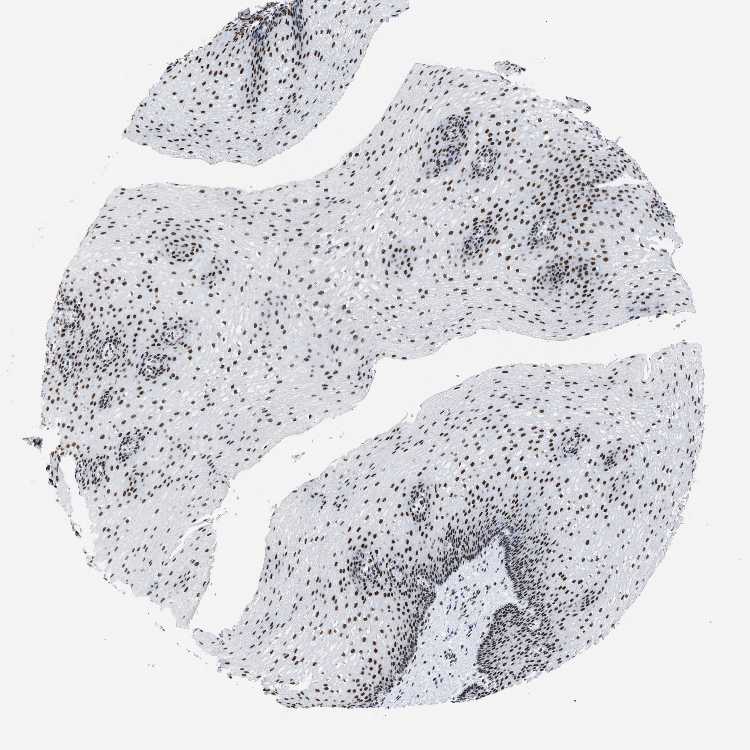

ESOPHAGUS - Antibody stainingi

Antibody staining in the annotated cell types in the current human tissue is reported as not detected, low, medium, or high, based on conventional immunohistochemistry profiling in selected tissues. This score is based on the combination of the staining intensity and fraction of stained cells.

Each image is clickable and will lead to virtual microscopy that enables deeper exploration of all samples and also displays staining intensity scores, fraction scores and subcellular localization as well as patient and tissue information for each sample.

Antibody HPA019907Antibody HPA019943Antibody CAB072827

Squamous epithelial cells HighHighHigh